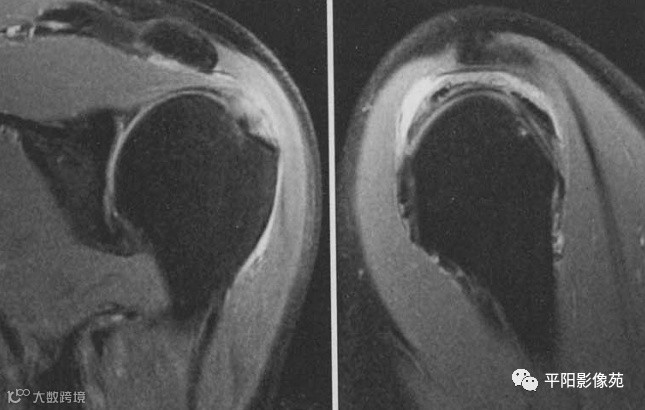

肌腱部分撕裂,示例

1、冈上肌肌腱关节面部分撕裂(Ⅲ级撕裂),造影剂进入肌腱

2、冈上肌肌腱滑囊面部分撕裂(Ⅲ级撕裂),肩峰下滑膜积液